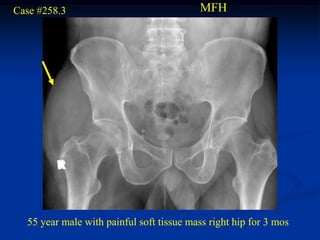

Case #258.3                               MFH

55 year male with painful soft tissue mass right hip for 3 mos

Cor T-1   T-2   T-2

Sag T-2

Thigh axial T-2

Pelvic axial T-2